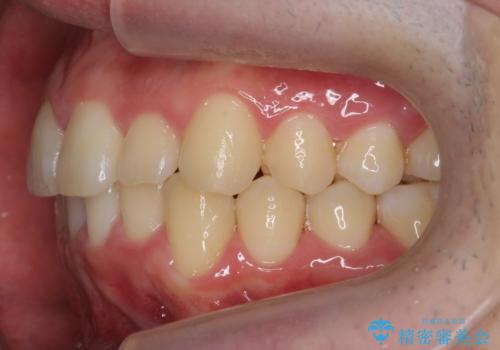

前歯のがたつき マウスピース矯正で 非抜歯で奥歯を後ろに下げる治療

- 前歯のがたつきを主訴に来院。

歯を抜かずに、奥歯を後ろに下げ、歯の両側をわずかに削って並べました。

奥歯を後ろに下げるのに、上下左右に矯正用ミニスクリューを入れています。

そのまま並べると戻りやすいのと、口元が出てしまうためです。

削る際も、拡大鏡を用いて精密に行っております。肉眼で削るのとは実は大きく差があります。

歯のがたつきがなくなると、歯ブラシがしやすくなり、茶色いステインも付きにくくなります。